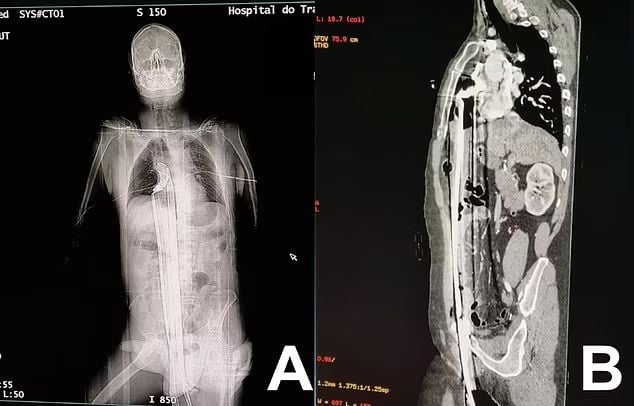

เมื่อวันที่ 17 กรกฎาคม เว็บไซต์ เดอะมิลเลอร์ ได้รายงานเหตุสยองหลังจากที่ชายชาวบราซิลวัย 57 พลัดตกลงมาจากนั่งร้าน เป็นความสูง 5 เมตร และถูกเหล็กแหลมยาว 60 เซนติเมตร แทงทะลุร่างกายตั้งแต่ทวารหนักถุงอัณฑะ ตับและส่วนหนึ่งของกะบังลม แต่เฉียดหัวใจไป

โดยชายคนดังกล่าวถูกรีบนำตัวส่งโรงพยาบาลภายในเมืองกูรีตีบาอย่างเร่งด่วน ก่อนจะนำแท่งเหล็กออกจากตัวได้อย่างปลอดภัย รวมถึงได้นำกล้ามเนื้อที่ได้รับความเสียหายออกด้วย